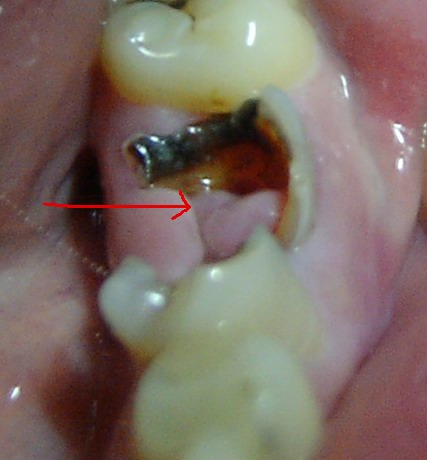

看来是你的牙龈组织长出来的息肉,到医院想办法处理一下,很小的手术

得了牙息肉(有图),能自愈吗?怎么治疗?要拨牙,要手术吗?

牙龈息肉多是牙龈乳头向龋洞增生所致.

【图】牙龈息肉图片 患者应该如何治疗?